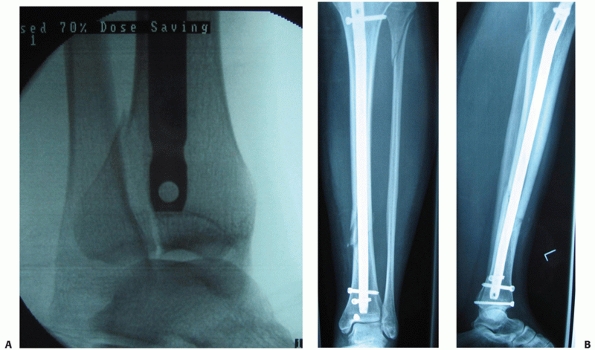

![]() |

FIGURE 55-9 A. An unstable OTA A3.3 fracture. B. It was treated successfully with a locked reamed intramedullary nail.